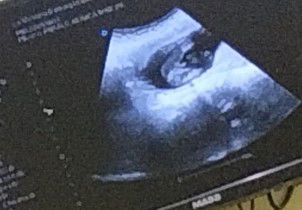

My 16weeks baby. Nagpakita na kaagad. It's a boy! Hehe.